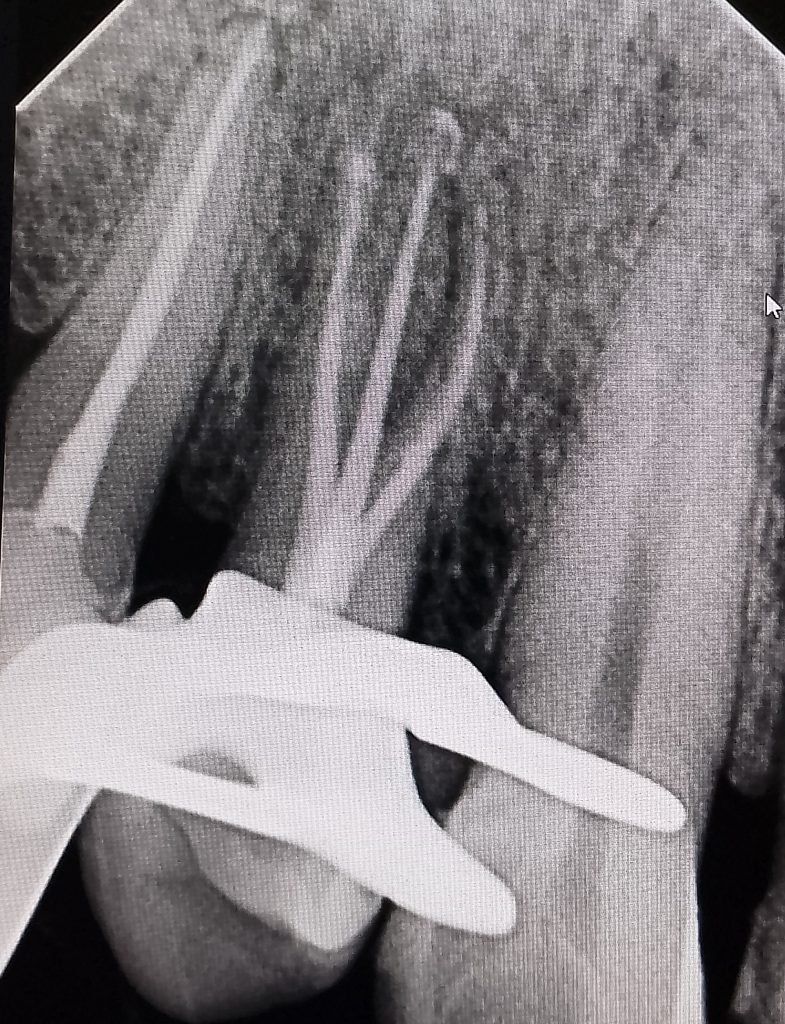

- Radiología Dental Utilizamos tecnología radiográfica digital para diagnósticos precisos de estructuras dentales no visibles en el examen clínico, con menor radiación.

- Endodoncia (Tratamiento de Conducto) Tratamiento especializado para salvar dientes cuyo nervio está dañado o infectado, eliminando el dolor y preservando la pieza dental.

Más de 20 años de experiencia en endodoncia garantizan resultados predecibles y duraderos